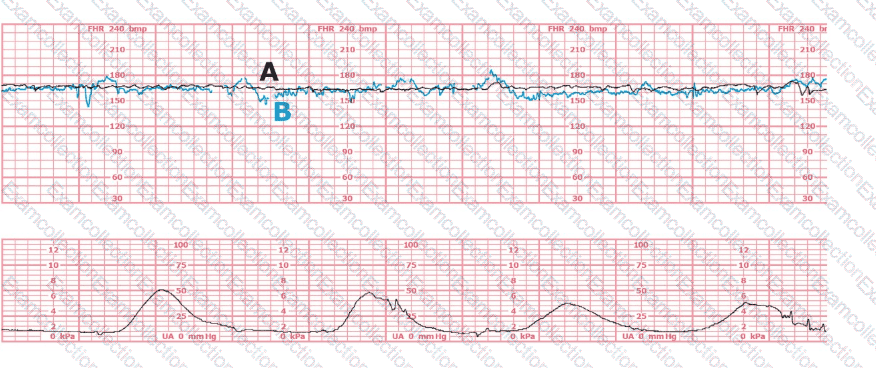

The tracing shows a clear relationship between uterine activity and fetal heart rate changes:

The uterine activity strip demonstrates very frequent contractions with little resting time between them, exceeding five contractions in 10 minutes, averaged over a 30-minute window.

As uterine activity intensifies and becomes excessively frequent, the fetal heart rate strip begins to show:

Progressive decrease in baseline

Recurrent decelerations with gradual onset and recovery

Reduced variability in the latter portion of the strip

This pattern is consistent with uteroplacental insufficiency caused by excessive uterine activity (tachysystole). NCC and AWHONN emphasize that tachysystole can result in decreased uterine blood flow and fetal oxygenation, leading to late or prolonged decelerations and eventual bradycardia if not corrected.